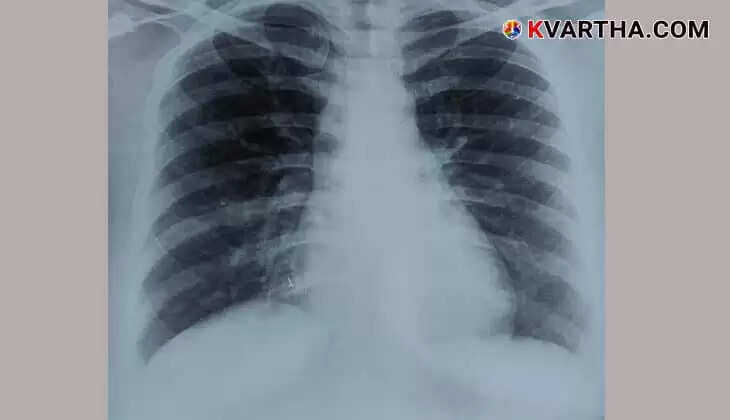

യുവതിക്ക് നടത്തിയ എക്സ്-റേ പരിശോധനയില്, നാല് വര്ഷം മുമ്പ് കാണാതായ മൂക്കുത്തിയുടെ ഒരു ചെറിയഭാഗം വലത്തെ ശ്വാസകോശത്തിന്റെ കീഴ്ഭാഗത്ത് തറച്ചിരിക്കുന്നതായി കണ്ടെത്തി. തുടര്ന്ന് വിദഗ്ധ ചികിത്സയ്ക്കായി യുവതിയെ അമൃത ആശുപത്രിയിലെത്തിച്ചു. അവിടെ റെസ്പിറേറ്ററി മെഡിസിന് വിഭാഗം മേധാവിയായ ഡോ. അസ്മിത മേത്തയുടെ നേതൃത്വത്തിലുള്ള വിദഗ്ധ മെഡികല് സംഘം സങ്കീര്ണമായ ശസ്ത്രക്രിയയിലൂടെ, മൂക്കുത്തിയുടെ ഭാഗം ശ്വാസകോശത്തില് നിന്ന് സുരക്ഷിതമായി നീക്കം ചെയ്തു.